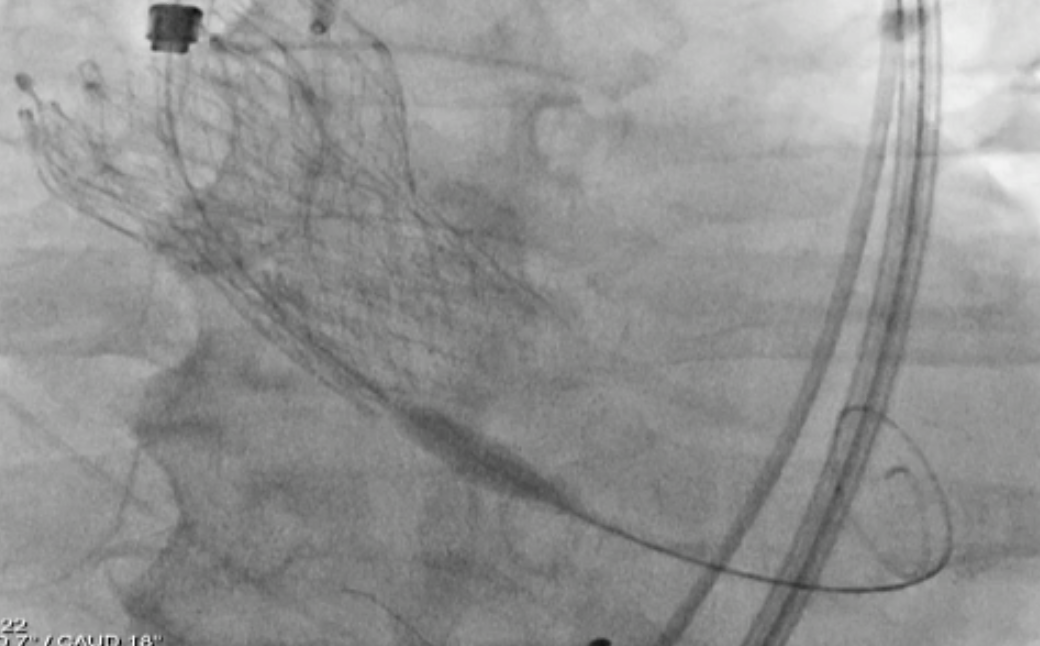

CT confirmed absence of commissural misalignment of failed CoreValve, and commissural alignment of the Evolut PRO was achieved by orienting the delivery system with the flush port at 3 o¡¯clock. The inflow portion of the the Evolut PRO was implanted at the same level as the failed CoreValve. Aortography post-implantation confirmed no RCA obstruction.

To mitigate the risk of coronary obstruction, the RCA was protected using a coronary guidewire and balloon. CT confirmed absence of commissural misalignment of failed CoreValve, and commissural alignment of the Evolut PRO was achieved by orienting the delivery system with the flush port at 3 o¡¯clock. The inflow portion of the the Evolut PRO was implanted at the same level as the failed CoreValve. Aortography post-implantation confirmed no RCA obstruction, allowing safe removal of the guidewire and balloon. The procedure was uneventful, with no conduction disturbances or paravalvular leak. The functional mitral regurgitation resolved immediately after the procedure.